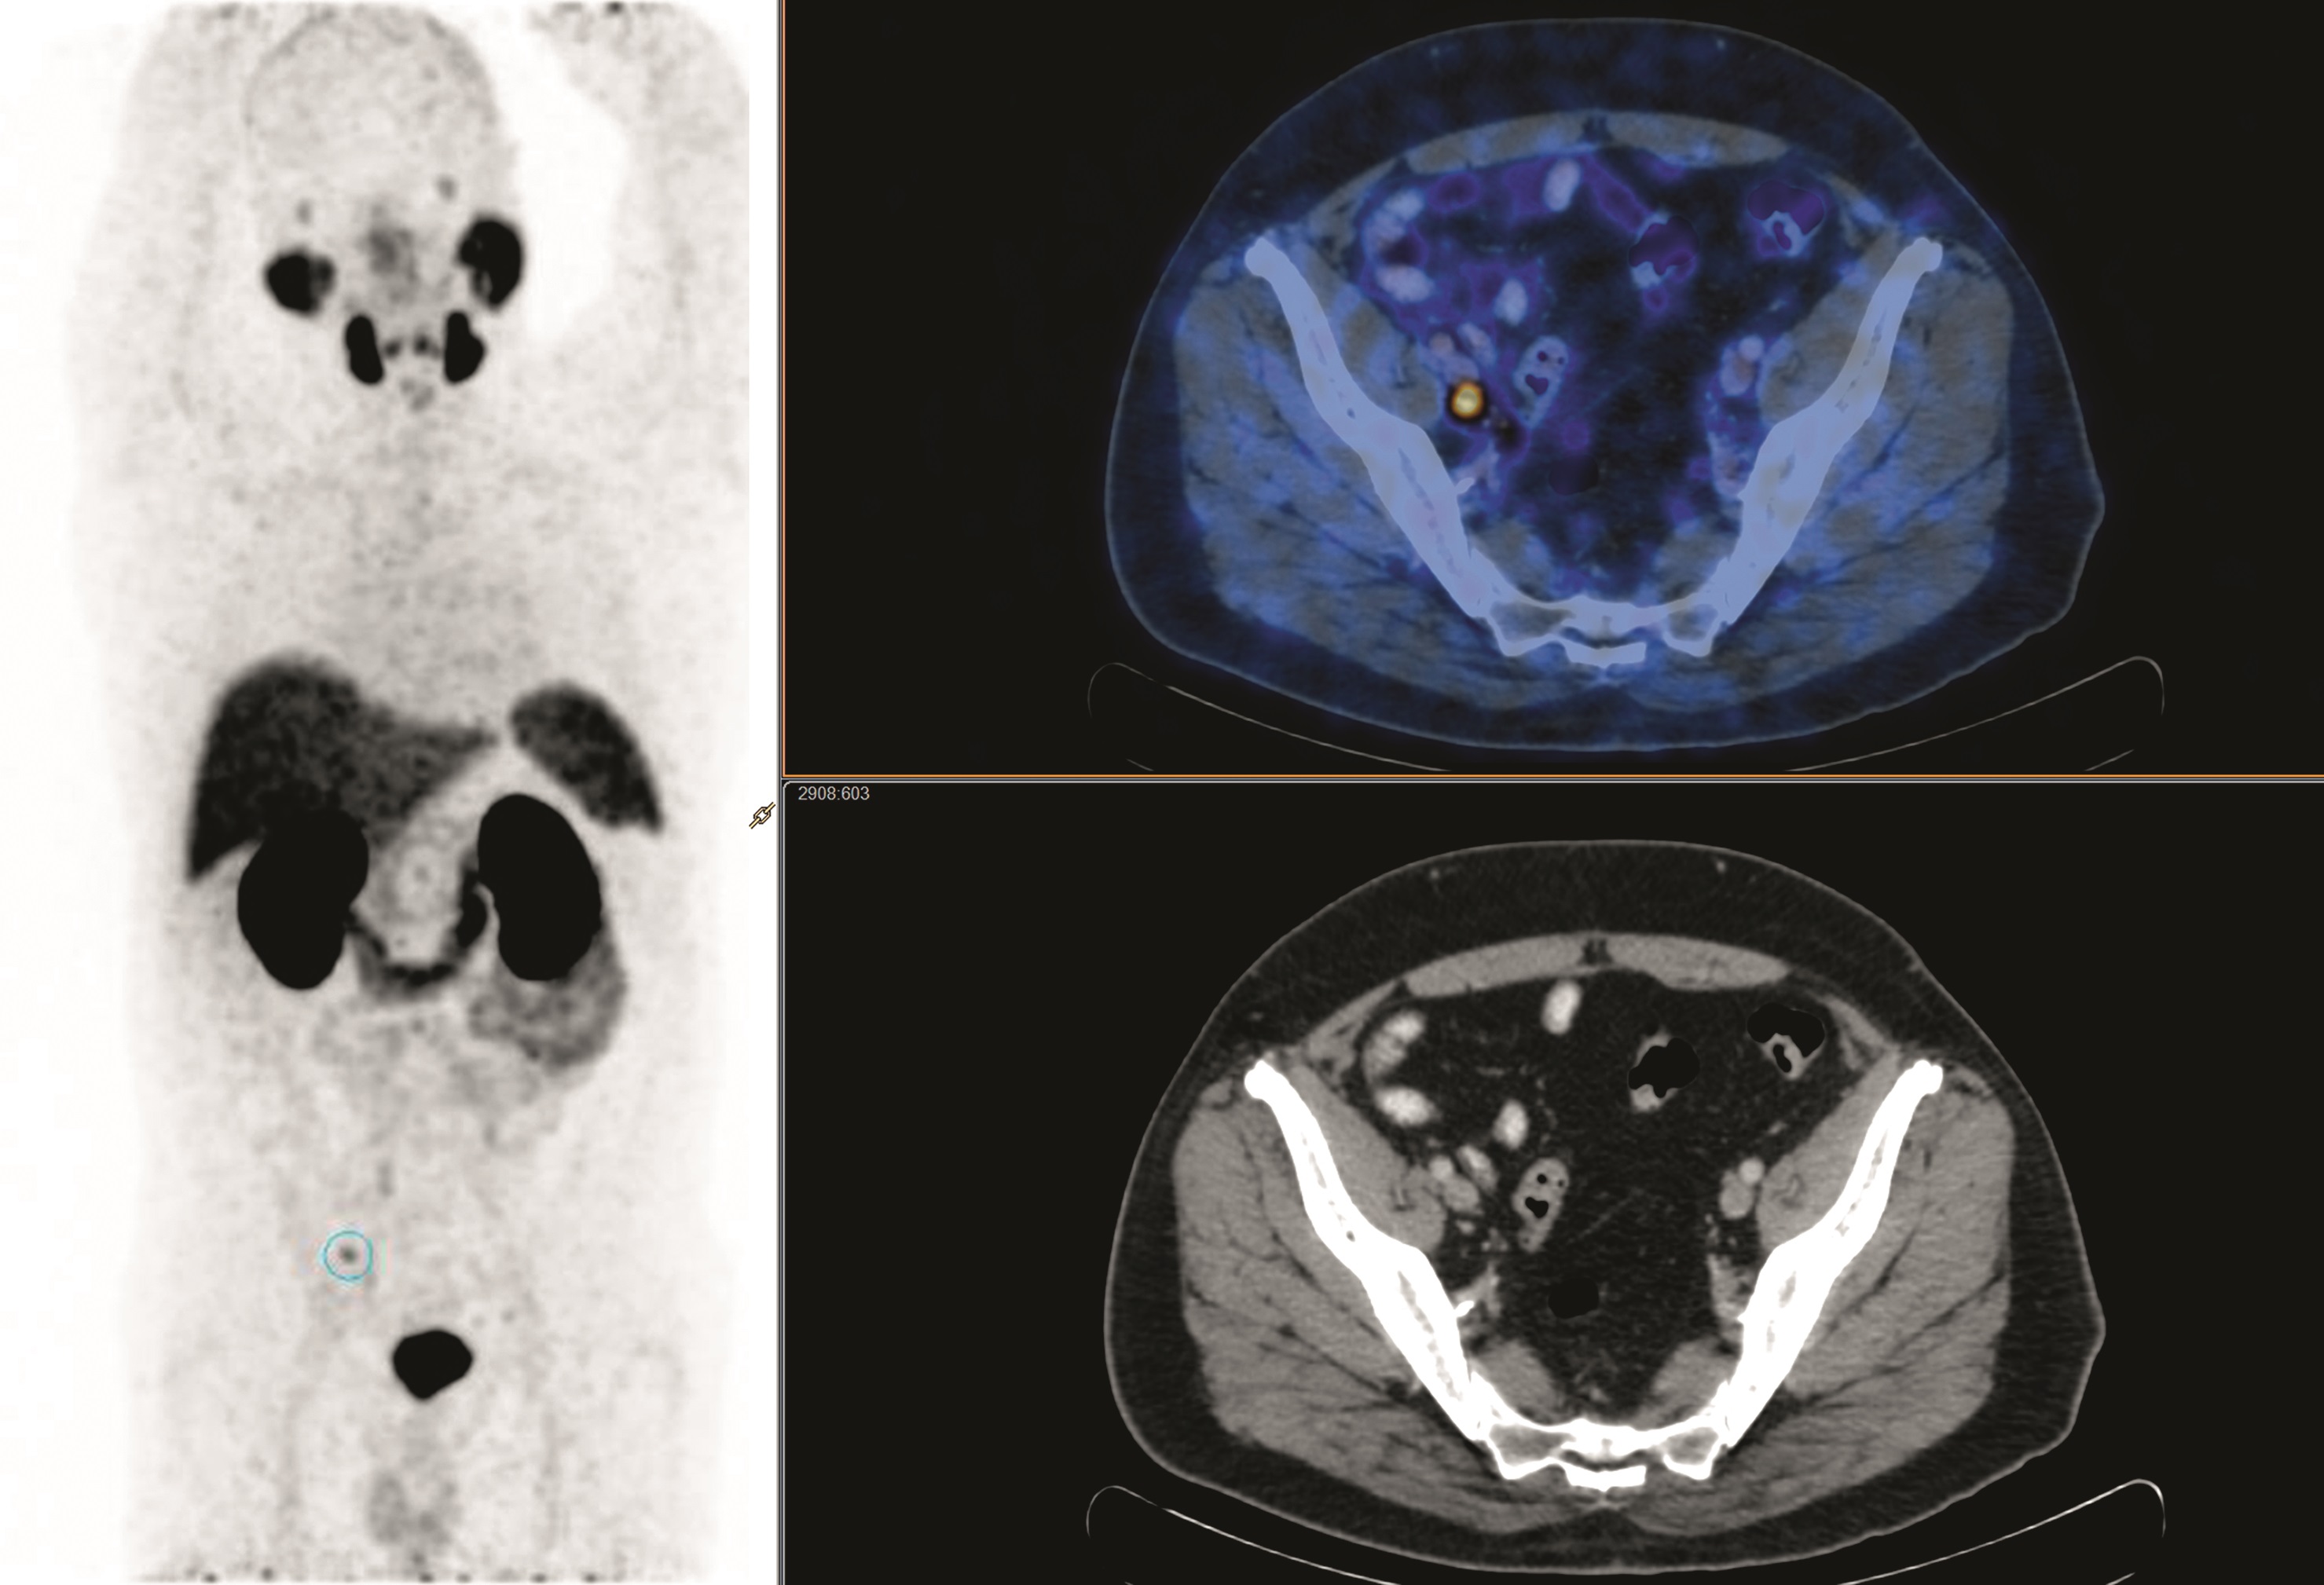

Prostate Cancer PET with 18FFDG, 18F or 11CAcetate, and 18F or 11C